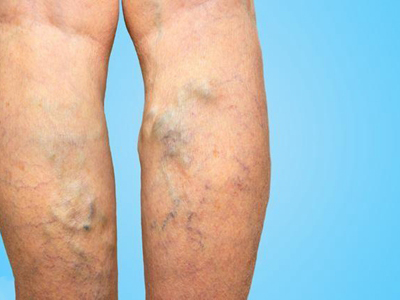

原发性大隐静脉曲张,又称为单纯性大隐静脉曲张,主要是由于静脉瓣功能不全、静脉壁薄弱等因素导致。可造成腿部酸胀不适、沉重、轻度疼痛,并伴有局部静脉隆起、扩张、迂曲等症状,严重时,可导致局部皮肤色素沉着、溃疡等情况发生。

原发性大隐静脉曲张开始时可无症状,随着静脉的扩张,因静脉外膜感受器受到刺激而有酸胀不适、沉重、轻度疼痛等症状,后期则以静脉曲张为主要表现,可在小腿前内侧出现浅静脉的隆起、扩张、迂曲,甚至蜷曲成团,站立时更为明显,有时还会蔓延至小腿后面。

此外,对于病程较长者,还会造成足靴区皮肤出现营养不良性变化,如皮肤萎缩、色素沉着,严重时还会造成局部溃疡的发生。